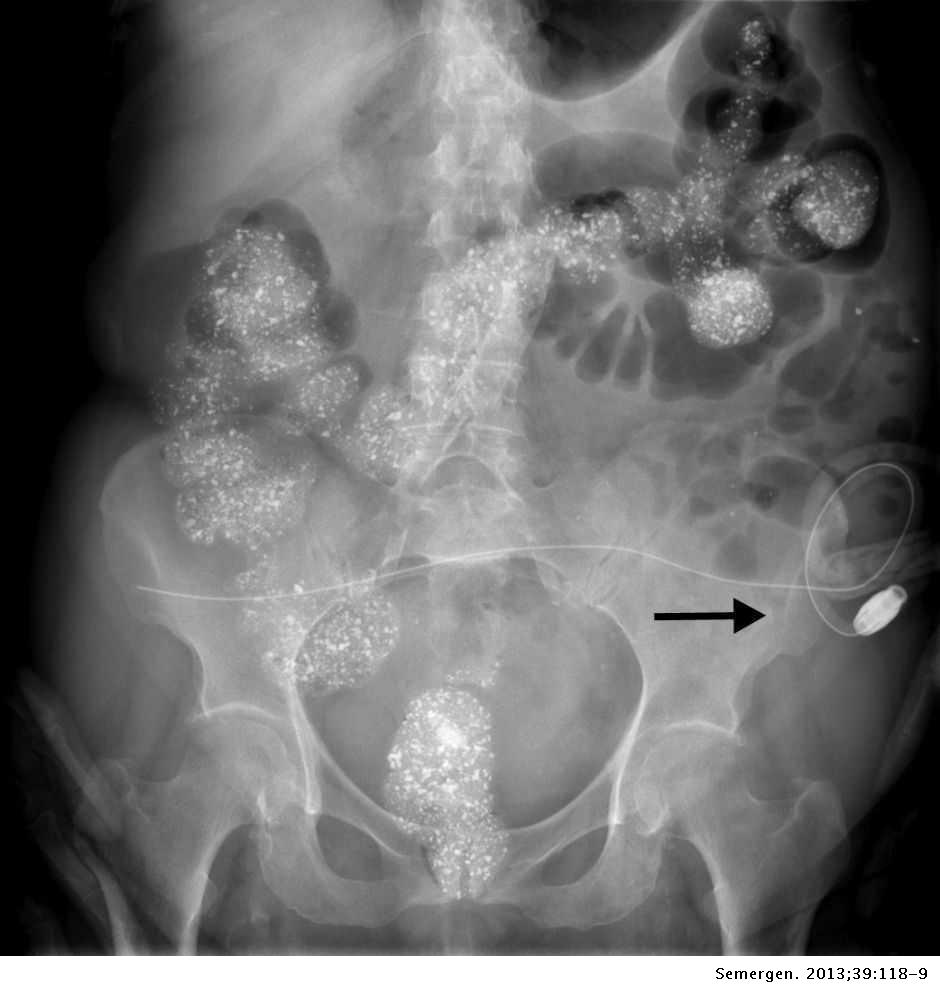

En medicina, el carbonato de lantano es un medicamento de acción quelante conocido como quelante de fosfato, vendido bajo el nombre comercial de Fosrenol por la compañía farmacéutica Shire Pharmaceuticals Group. Se prescribe para el tratamiento de la hiperfosfatemia, primariamente para pacientes con insuficiencia renal crónica. Se toma con las comidas y se enlaza con el fosfato de la dieta, evitando que el fosfato sea absorbido por el intestino.